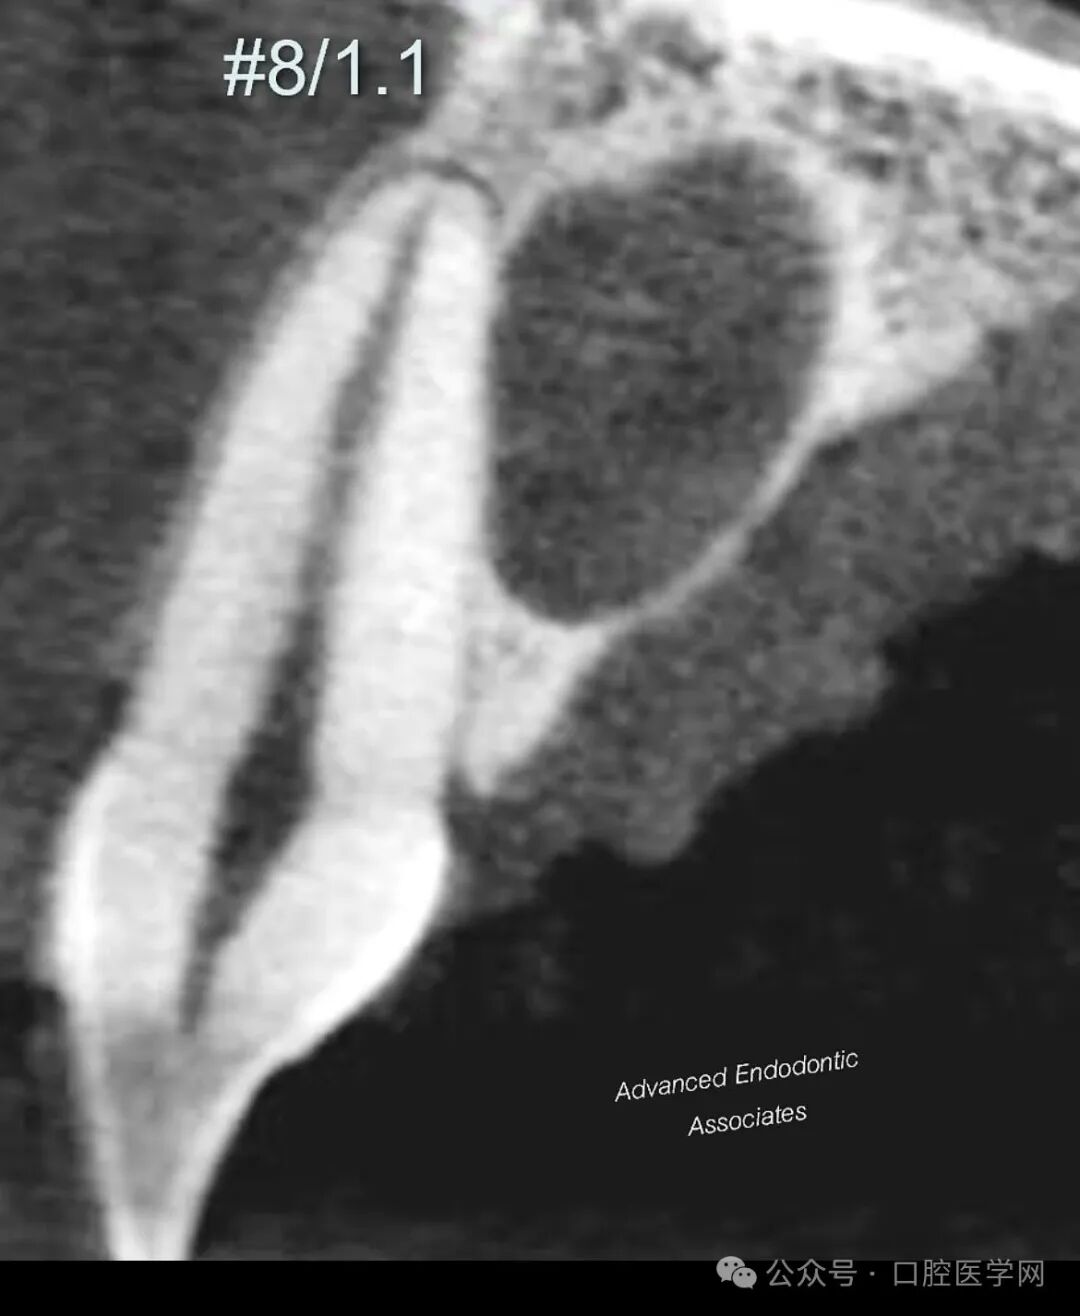

1. 完整的牙周膜(PDL):放射片显示病变区域内牙周膜结构完整。需特别注意,若在病变区域内可清晰追踪到牙周膜影像,表明该病变与牙根表面关联的可能性极低。

结合上述影像学特征及CBCT评估,我们明确诊断为“切牙管囊肿”。患者随后被转诊至口腔颌面外科医生处,进行进一步随访及治疗。